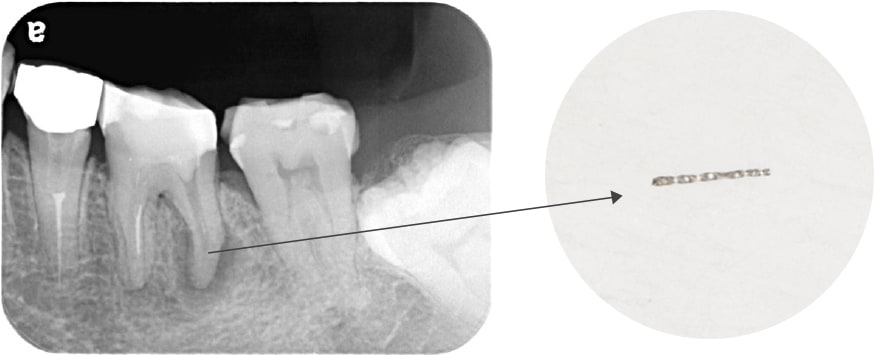

近所のかかりつけの歯科医院で、「再治療できないから奥歯を抜くしかない」と言われた。

あきらめきれず、HPで探して当院へ来院。

折れて残っていた機具を除去

根管の中を洗浄し、無菌に近い空の状態にした。

根管の中を封鎖し終了。

治療後病気がなくなり骨が再生した